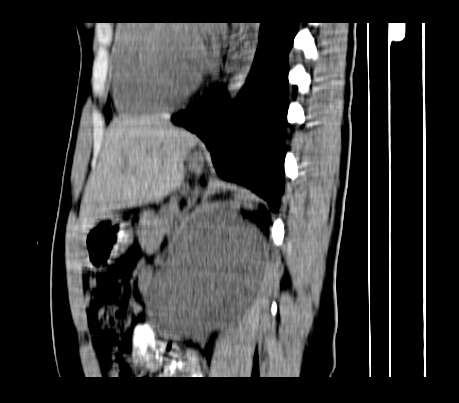

重建